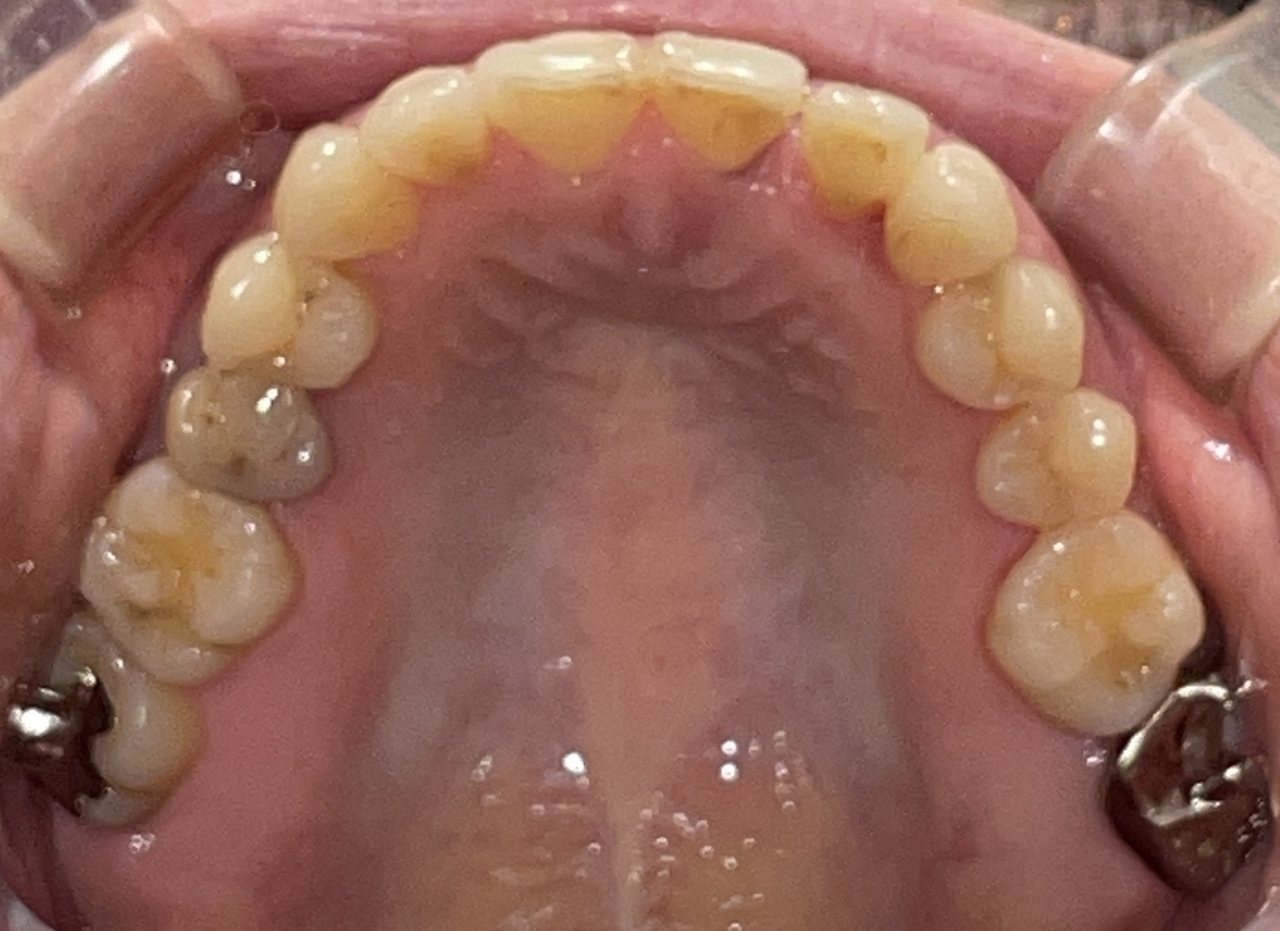

Before

After

矯正の種類 / invisalign GO

年齢・性別 / 30代女性

主訴  /  叢生、交叉咬合

治療期間 / 17ヶ月

費用 / 簡易検査 5,000円(税別) 精密検査 30,000円(税別)

両顎マウスピース 450,000円(税別) 両顎リテイナー料 60,000円(税別)

※マウスピース交換時別途調節料5,000円(税別)

副作用 / 口内炎・歯の移動に伴う痛み・知覚過敏 ※数日で収まる場合が多いです

リスク / 後戻り防止の為、夜のみマウスピースで保定を指示